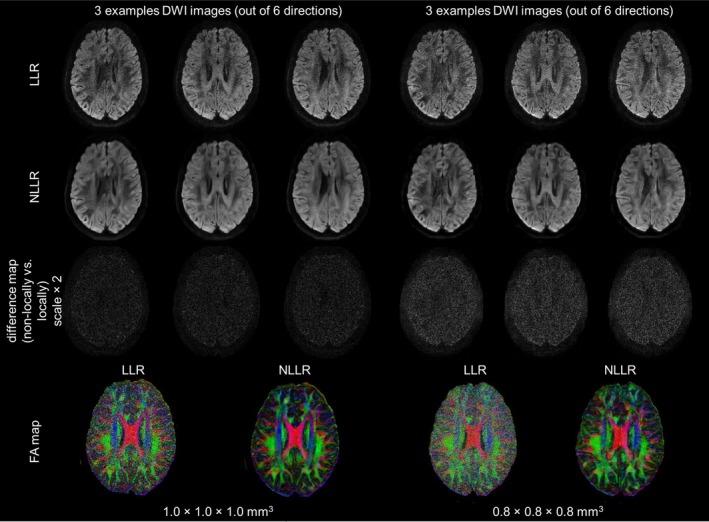

In simulation experiments, compared to post-processing denoising algorithms, NLLR demonstrated superior noise suppression and structural preservation across all metrics, even when reconstructing from a single diffusion direction. In the in-vivo experiments, NLLR outperformed conventional navigator-free approaches particularly regarding noise suppression. Fractional anisotropy maps reconstructed using NLLR exhibited improved visualization of fine structures with improved SNR, with performance differences becoming more pronounced at higher resolutions.

在模拟实验中,与后处理去噪算法相比,NLLR在所有指标上均表现出卓越的噪声抑制和结构保留能力,即使从单个扩散方向进行重建时也是如此。在体内实验中,NLLR在噪声抑制方面尤其优于传统的无导航器方法。使用NLLR重建的分数各向异性图在提高信噪比的情况下,对精细结构的可视化效果得到改善,在更高分辨率下性能差异更为明显。